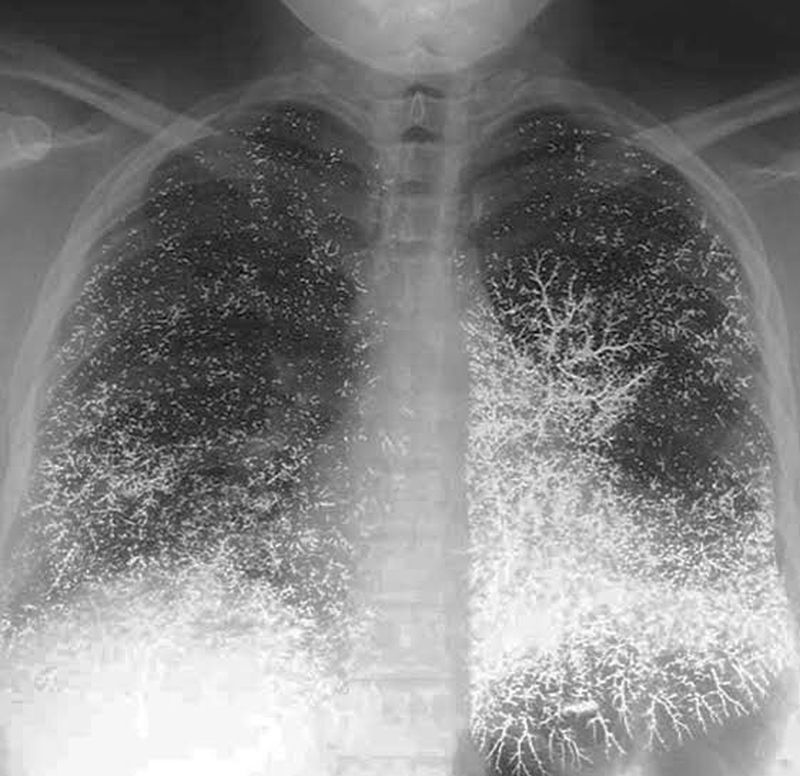

What’s this???

Difficulty in breathing

Looks like a case I saw elsewhere with attempted suicide by ingestion of mercury

Mercury poisoning

Mercury pulmonary empolisn